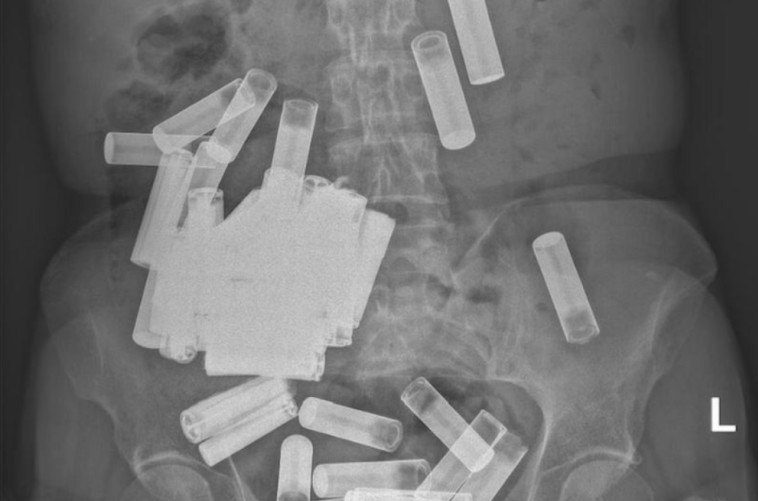

מקרה חריג אירע לפני מספר ימים בבית חולים אוניברסיטאי בדבלין. אישה פנתה לטיפול רפואי לאחר שסבלה מכאבים עזים והתכווצויות בבטן. לאחר מספר בדיקות, הרופאים נותרו בהלם ממה שהתגלה

למרבה המזל, כך לפי הדו"ח הרפואי, אף אחד מהעצמים הזרים לא חסם את מערכת העיכול של בת ה-66 והצוותים קיוו שהם יעשו את דרכם החוצה "באופן טבעי וללא התערבות כירורגית", כך דיווח Live Science. עוד נמסר כי בשבוע הראשון הצליחה האישה להיפתר מחמש מתוך 55 הסוללות שהיו בבטנה "בדרך טבעית", אך השאר נותרו תקועות.

מדובר בית החולים נמסר: "למיטב ידיעתנו, במקרה הזה נתקלנו במספר הסוללות הגבוה ביותר שהיה אי פעם בבטנו של אדם". למרות שהתקרית עוררה סקרנות רבה לגבי כיצד הגיעו הסוללת לבטנה של האישה, בית החולים התייחס לבליעת סוללות והסביר כי מדובר בשיטה קטלנית וחמורה לפגיעה עצמית. הצוותים סבורים כי בת ה-66 החדירה את העצמים דרך פי הטבעת והן עלו במעלה המעי.

"המטופלת ניצלה בנס. מקרים מסוג זה עלולים לגרום לפגיעות חמורות כגון חסימת המעי, ניקוב, פגיעה ברירית, ומקרי חירום כירורגים חריפים". ובשורה התחתונה, לא לנסות את זה בבית.